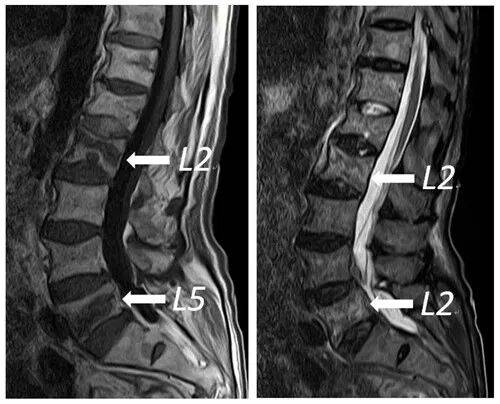

4.脊柱MRI检查:当涉及单一或者多椎体时,MRI检查也可作为骨质疏松症及骨质疏松性骨折的检查方式之一。MRI可通过不同的信号区分新鲜或陈旧的骨折,也可通过椎体内信号差异预测骨质疏松性骨折的发生。

图2.腰椎MRI显示腰2、腰5椎体压缩骨折